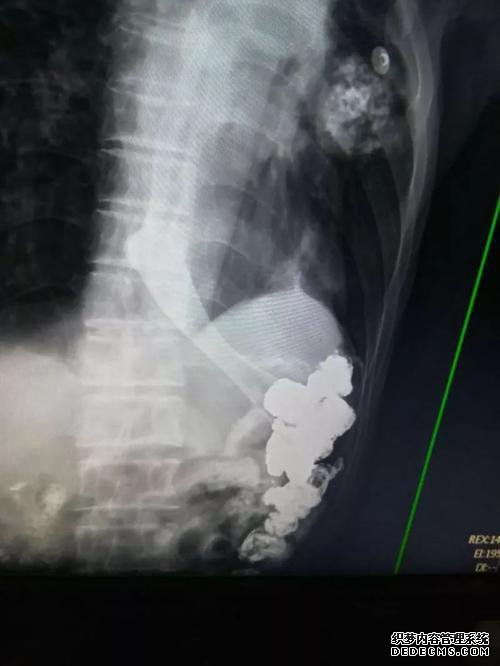

钡食物检查主要是胃肠道检查的方法,即先做相关准备工作,然后用X射线照射的检查。此类考试的费用因考试地点而异,并且会有所不同。

检查消化道通常在200元左右。观察消化道的费用通常在300元左右。

尽管钡餐检测非常安全,但该疾病的诊断不如胃肠道内窥镜检查准确,但它也可以有效地检测出胃肠道疾病。

在钡饮食测试期间,患者没有疼痛或其他并发症。